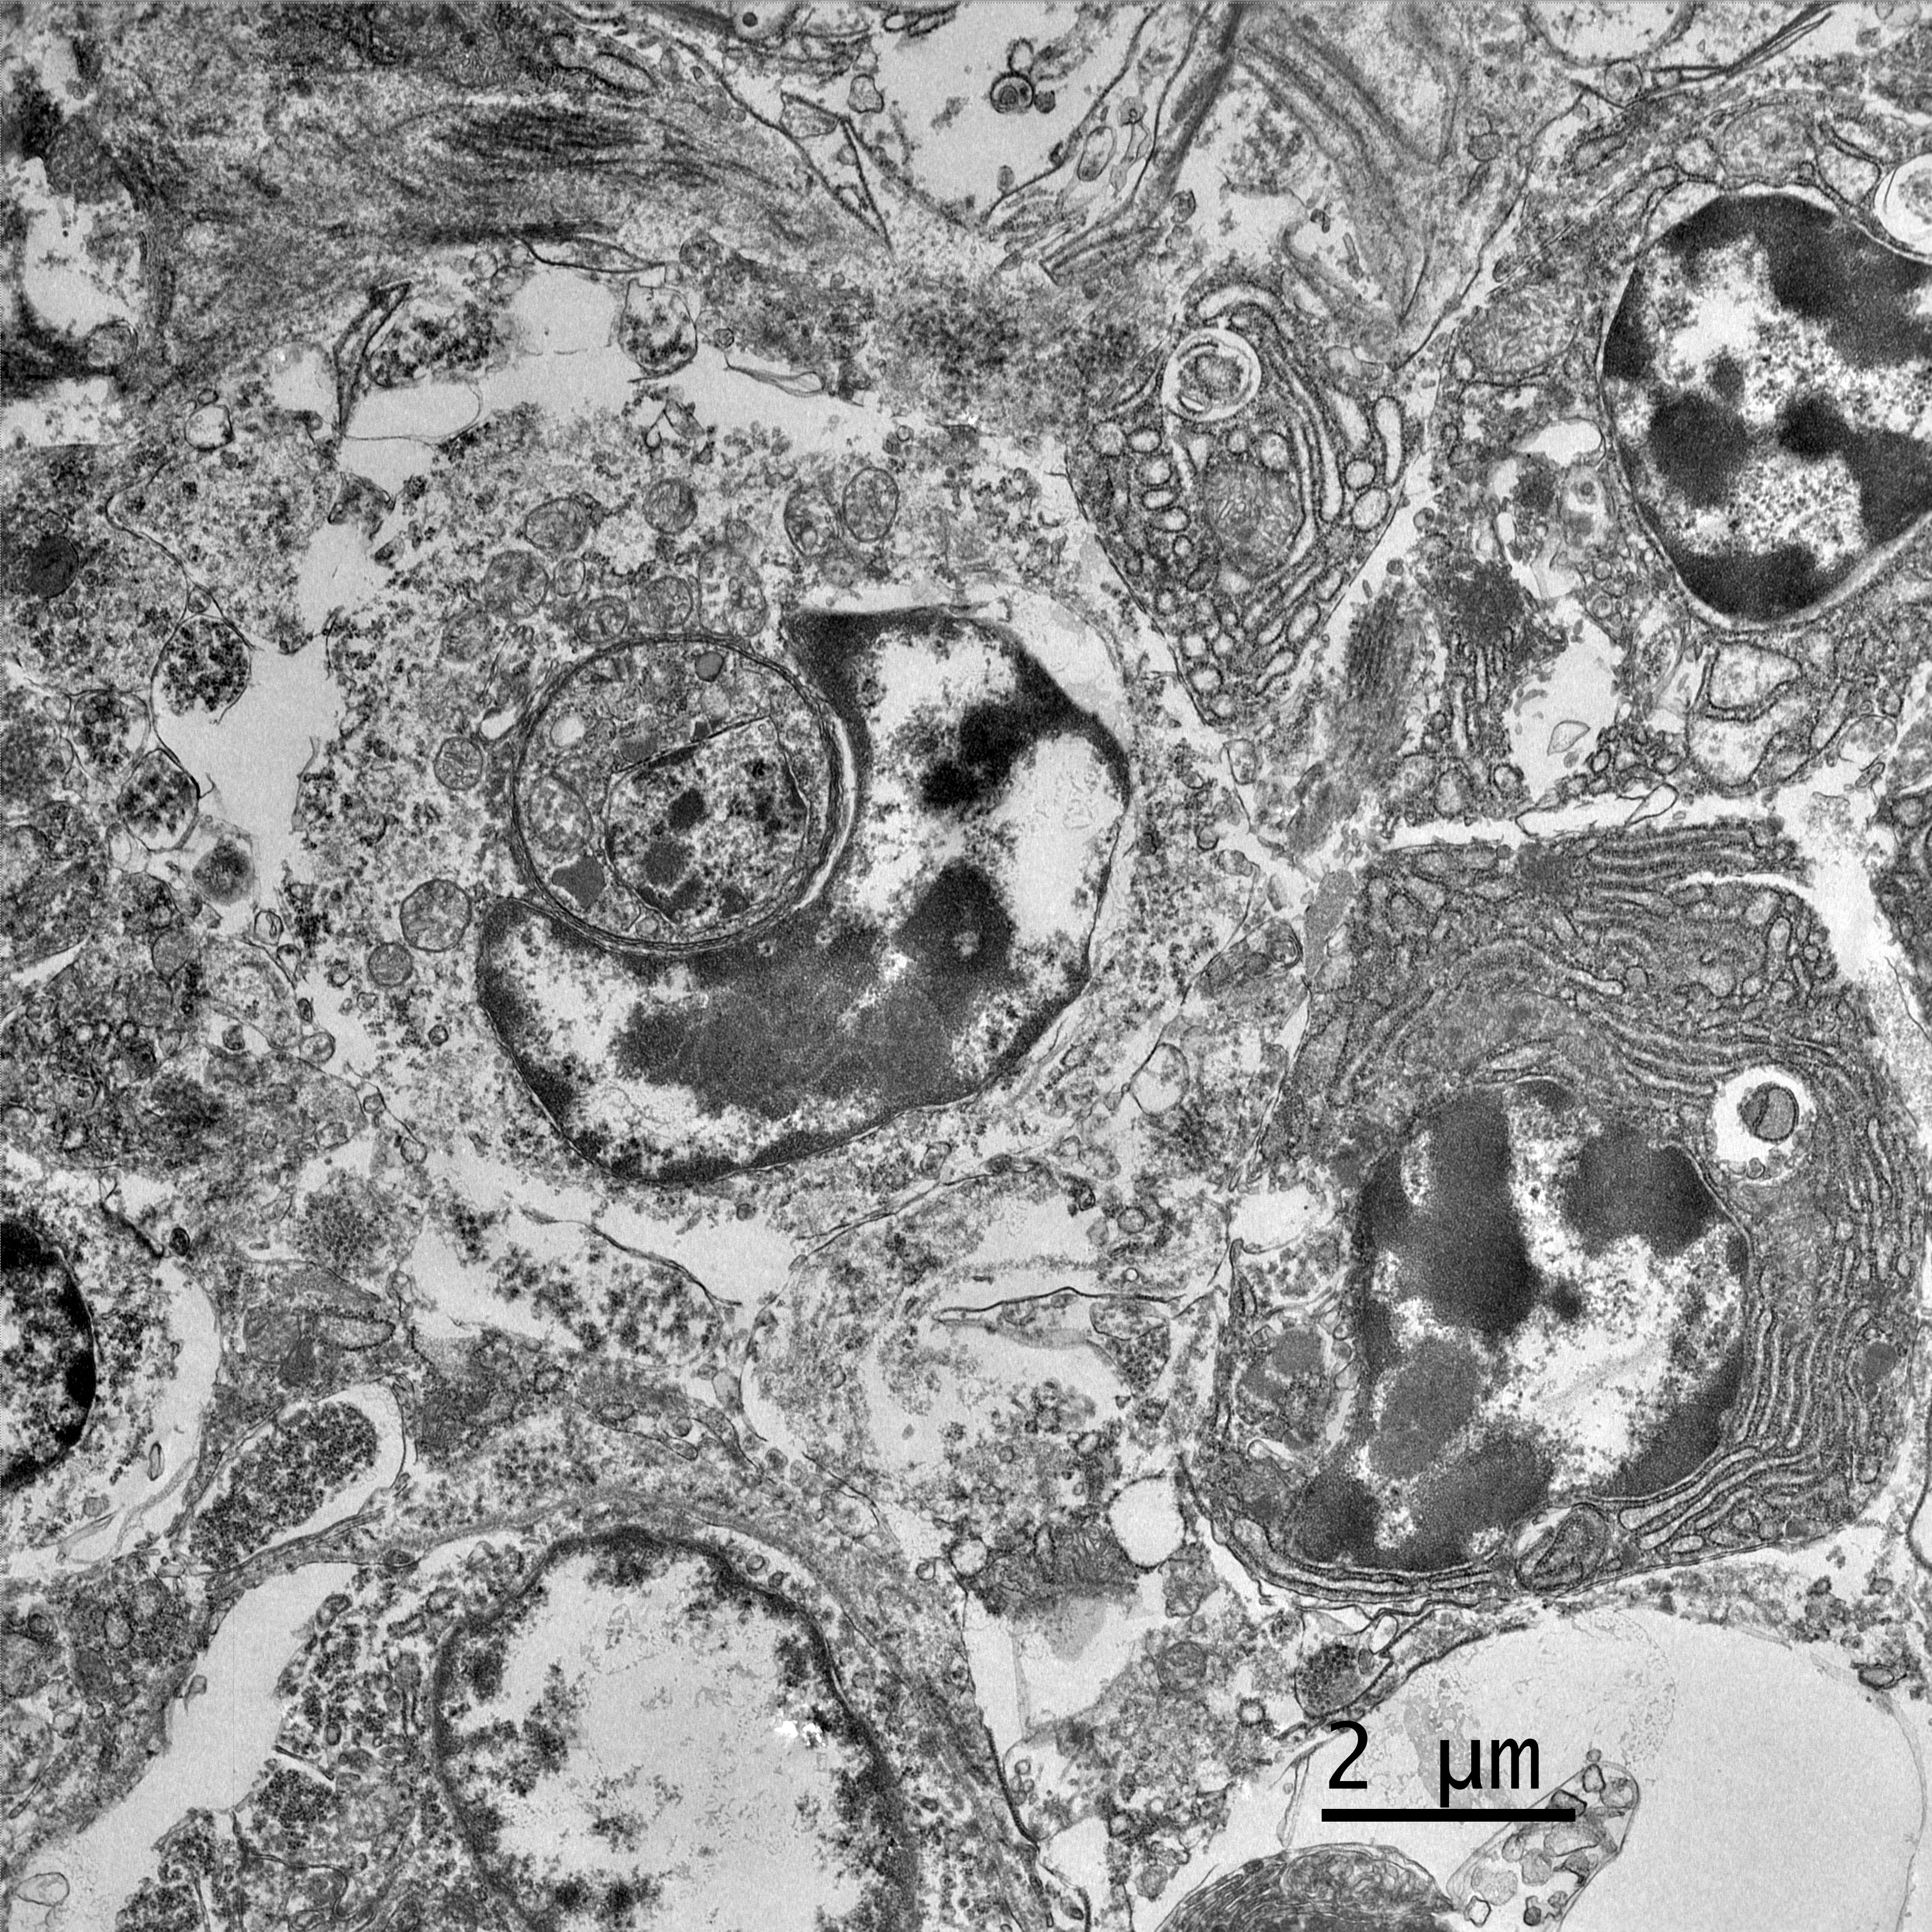

Electron microscopy, California Animal Health and Food Safety Lab in Davis, CA (formalin-fixed liver):

- Free organisms- family Trichomonadidae flagellates with 5 apical flagella (one recurrent)

- Lymphocytes- Intracytoplasmic Isospora

Present in often very large numbers throughout the vasculature were extracellular protozoa consistent with flagellates that could have contributed to the inflammation in some tissues. Using a trichomonad PCR assay, sequences with a closest match to Cochlosoma anatis were obtained from both lung and intestine, although identity was only ~93%. Electron microscopy of liver tissue confirmed intracellular protozoa consistent with Isospora, and extracellular flagellates consistent with tetratrichomonads based on the presence of 5 undulipodia at the apical pole with one recurrent. In contrast, Cochlosoma sp. have six flagella, one of which is recurrent. Both Cochlosoma and Trichomonas have a single nucleus, a parabasal apparatus, a tubular axostyle, and a crescent-shaped pelta.6 Prior studies have identified via sequence analysis of the 16S rRNA gene that Cochlosoma and Trichomonas are genetically similar, which likely accounts for the 93% identity match.4Tetratrichomonas and C. anatis are often identified with other intestinal pathogens and their pathogenicity as a sole pathogen remains uncertain.1,4 Both have been documented as the cause of fulminant disease in a variety of birds. Tetratrichomoniasishas been identified as the causative agent of acute typhlohepatitis in ducks, a necrotizing hepatitis and splenitis in a Waldrapp ibis and necrotizing hepatitis in a free-ranging white pelican.1,2Cochlosoma anatis is linked to enteritis in turkeys, as well as increased dehydration, malabsorption, and mortality in young finches.4 However, prior studies have failed to document clinical signs or histologic lesions in experimental infections with Trichomonas and coinfections of Cochlosoma with other intestinal pathogens have demonstrated greater pathogenicity than with either pathogen alone.1,4

Finally, Dr. Pesavento quizzed participants on the ultrastructural images from this case, which was an appreciated, succinct review for many attendees. Key takeaways from this discussion included trusting your anchors (i.e. erythrocytes, nuclei, etc.), determining the number of cell profiles in the EM image, and knowing what normal looks like so you can evaluate the abnormal. The protozoal organisms on EM had some key characteristics to look for, as well, including the flagella on the Trichomonads with their classic microtubule 9+2 arrangement, and the apicomplexan conoid, rhoptries, and micronemes within the Isospora.5,6 Her last piece of wisdom in this case regarded microvilli on EM: don't call them microvilli unless you can see the actin microfilaments holding them up. If not, they are termed "cellular projections."